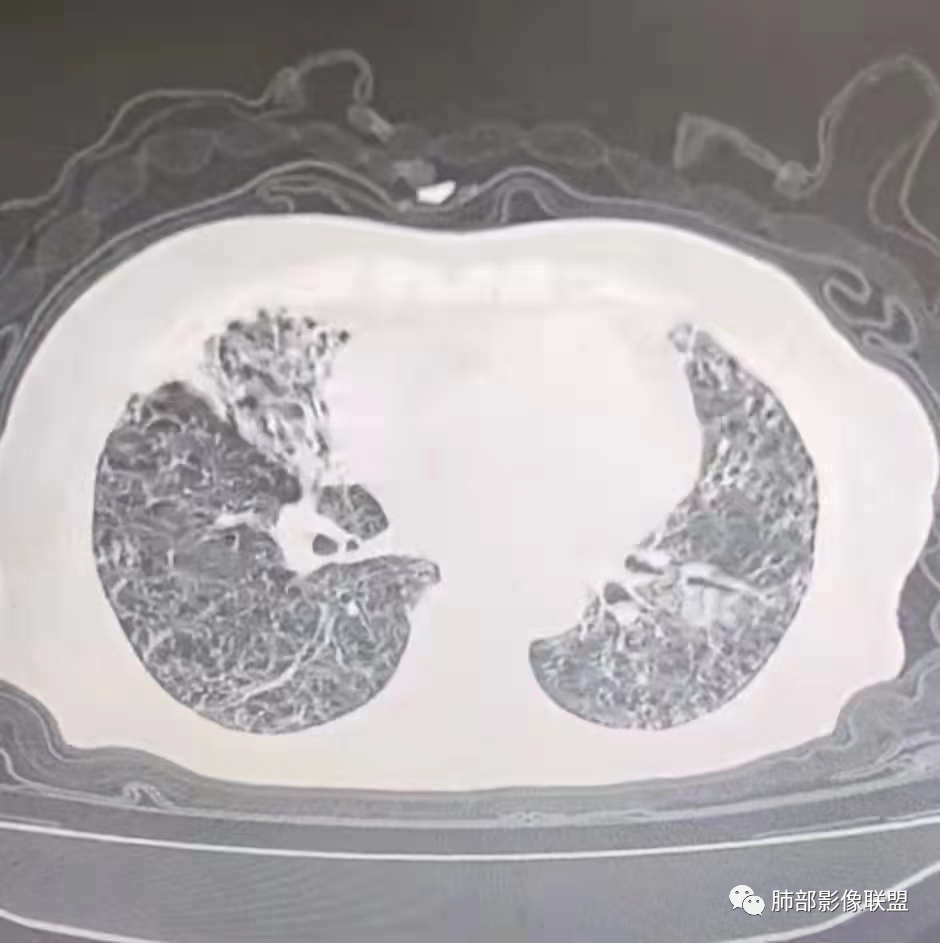

2、影像特点:右肺中叶、左肺下舌段可见支扩。左肺下舌段及两肺下叶可见片状实变影及发结节影,病灶边界多显示不清,纵隔窗显示病灶密度较均匀,未见液化、空洞或钙化。左肺下叶部分病灶沿支气管分布,并可见局部支气管管壁增厚。

3、患者以前多次发生左侧肺炎,但未提供既往的影像资料。推测患者肺部多次感染与支扩或者同侧其他支气管病变相关。病灶区域左肺支气管管壁增厚,并可见沿支气管分布的斑片影,提示病灶来源于气道,符合感染性病变影像学表现。临床及影像的难点在于当前责任病原菌的查找及推断:

2)病灶密度较均匀柔和,边界不清,没有树芽征,没有新旧不等,病情反复,吸收变化较快,显然不符合结核或非结核分枝杆菌感染。

事实上,支气管扩张患者可以伴发多重感染,不同时期,责任病原菌也许并不相同。